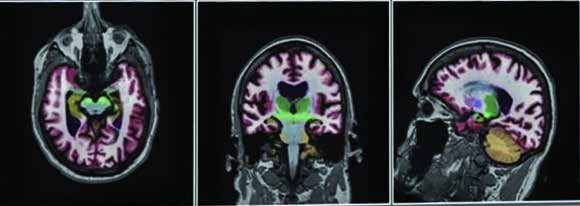

SimonMed Imaging’s new Neuro Degenerative Diagnostic Centers are now offering NeuroQuant quantitative

MRI measurement software as a routine part of SimonMed’s neurodegenerative imaging practice.

NeuroQuant™ is the leading FDA-cleared, fully automated quantitative brain imaging analysis software

which provides high-resolution 3D volumetric analysis of subcortical brain structures and compares them to

a normative database ranging in age from 3-100.

NeuroQuant generates an almost instantaneous color-coded

3D data set of anatomic brain structures along with three graphic volumetric data reports of the patient’s

quantitative brain analysis compared with age-matched controls.